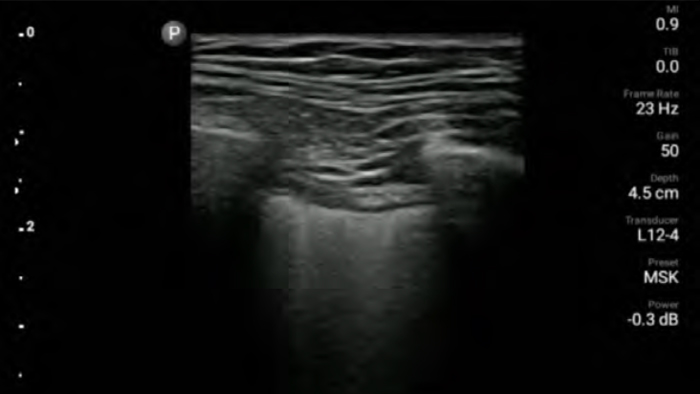

Bring ultrasound bedside

Using Lumify at your patients bedside can be a valuable tool to determine the status of stomach contents and can lower the risk of pulmonary aspiration. Together, this can reduce the risk of anesthesia complications.